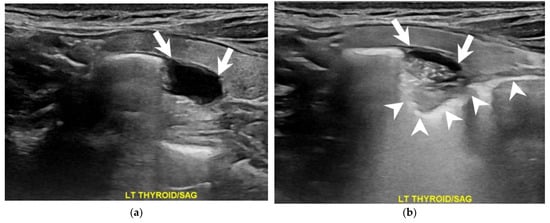

How Soda Ingestion Facilitates the Distinction between a Killian–Jamieson Diverticulum and a Malignant Thyroid Nodule